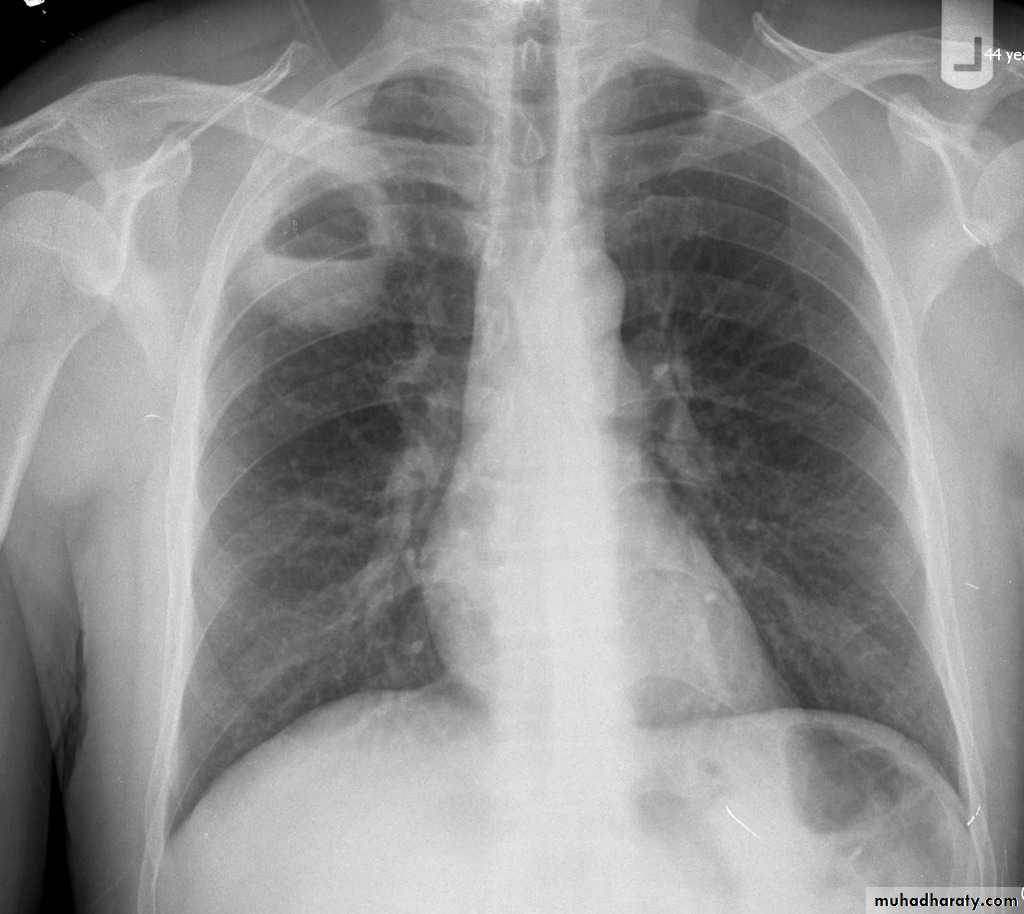

Pulmonary emphysema is defined as the "abnormal permanent enlargement of the airspaces distal to the terminal bronchioles accompanied by destruction of the alveolar wall and without obvious fibrosis". Emphysema is one of the entities grouped together as chronic obstructive pulmonary diseaseRadiographic features

Plain filmExcept in the case of very advanced disease with bulla formation, chest radiography does not image emphysema directly, but rather infers the diagnosis due to associated features :

hyperinflation:

1.flattened hemidiaphragm(s): most reliable sign

2.ncreased and usually irregular radiolucency of the lungs

3.increased retrosternal airspace

4.increased antero-posterior diameter of chest

5.widely spaced ribs

6.sternal bowing

7.tenting of the diaphragm

8.saber-sheath trachea

9.vascular changes paucity of blood vessels ( absent pulmonary markings in outer 1/3 of the lung fields )

10 .pulmonary arterial hypertension

pruning of peripheral vessels

increased calibre of central arteries

right ventricular enlargement